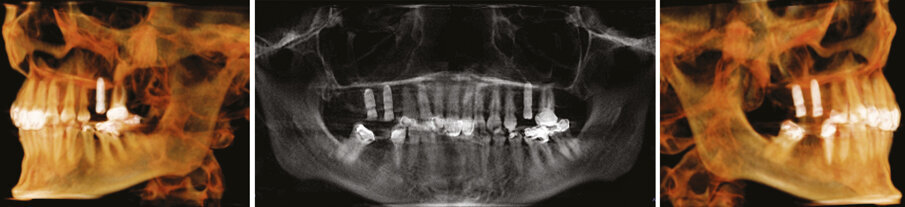

Figs.1-2: Pre Op situation upper right and left sides.

Figs.22-24: Final CT reconstructions and Pan xray.